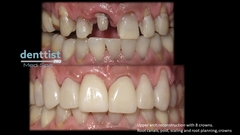

Galería Dental

Coronas de Porcelana